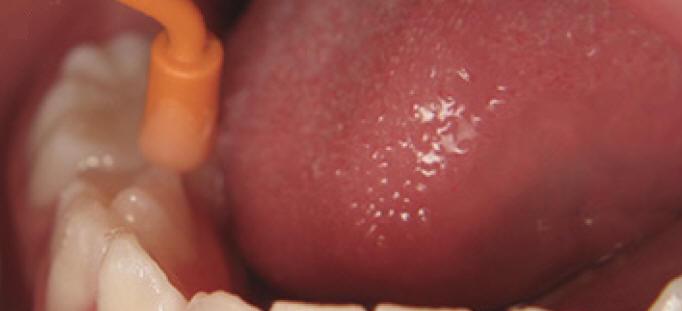

Imagen digital que representa la microfiltración y penetración del sellante realizado.

Microfotografía: Muestra como el sellador obtura la caries subyascente, evitando su avance.

Código 3 (Caries moderada) in vitro. Los códigos 3 in vivo debe ser sellado para evitar el avance del proceso carioso. (MNO)

Código 4 (Caries moderada) in vitro. Los códigos 4 in vivo deben ser tratados en forma operatoria con preservación dental (MOPD), porque presentan dentina infectada.